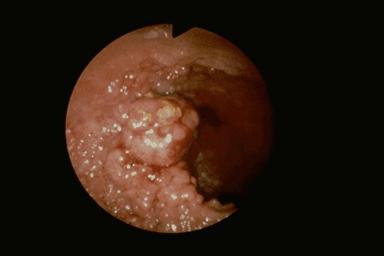

Caso de "Lesión nódulo agregante" acompañado de Cáncer Avanzado de Colon en la región central

[Image-ID:1377]

parte(separada por órganos)

colon/recto

método de exámen

Endoscopia

diámetro mayor del tumor

40 -

grado de penetración

mp